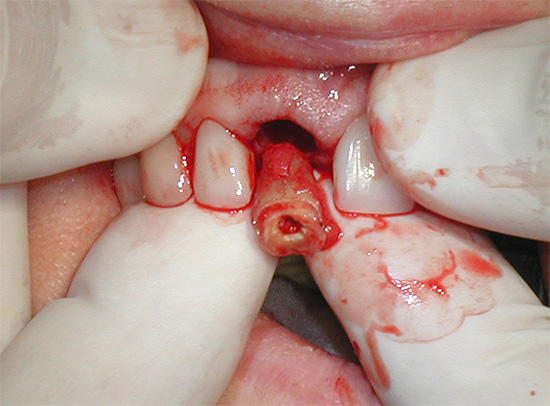

Táticas de tratamento.Para eliminar fontes diretas de dor na forma de inflamação das raízes no topo, foi realizado um tratamento em fases:

- Dissecção com boro através da coroa;

- Abertura da boca do canal na raiz anterior problemática;

- Passagem e expansão do canal, não atingindo o ápice em 20-30%;

- Vedação com obturadores de núcleo mole no comprimento necessário;

- Ressecção (recorte) do topo da raiz anterior;

- Controle as imagens após o tratamento e após um ano;

- Coroas de substituição.